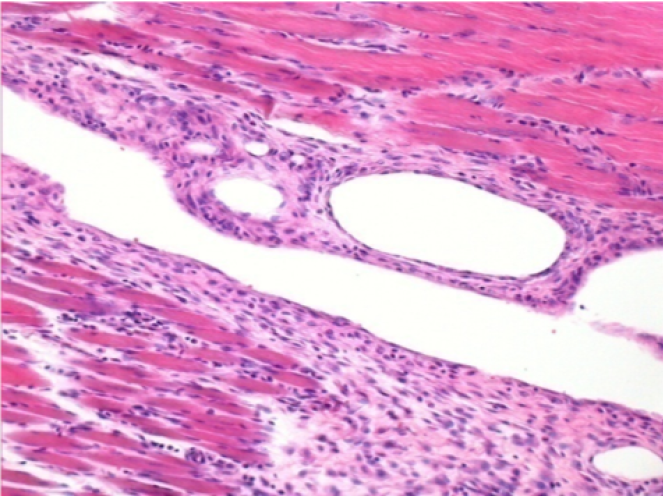

1 month after Endopeel Injection 0.1ml in the right pretibial muscle.

What is seen in black on the pictures is not a necrosis like could imagine some scientifics !

In fact, 4 conclusions have to be taken in consideration